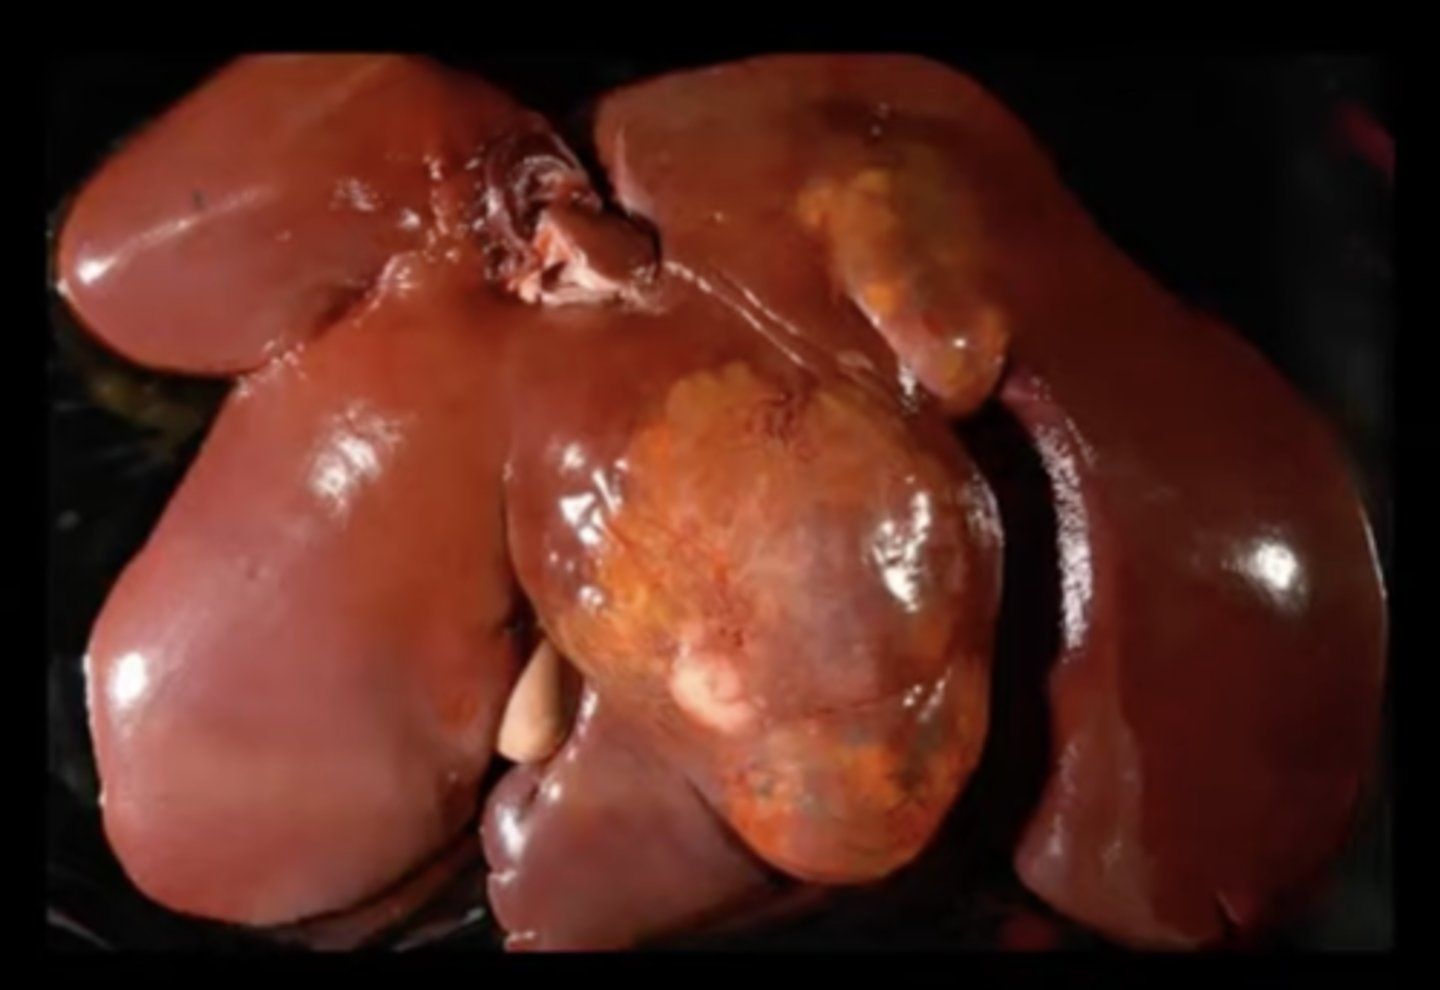

Hepatocellular carcinoma

-firm tissue

-malignant

-

What has caused this gross appearance of this liver?

Hepatocellular carcinoma

What has caused this gross appearance of this liver?